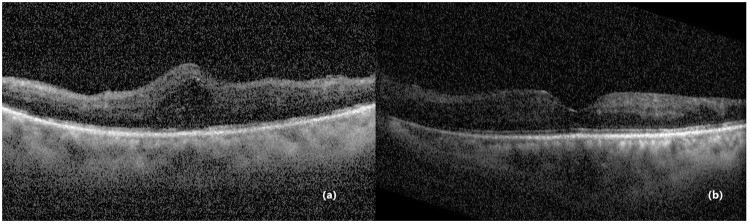

Case presentation: A 63-year-old male developed bilateral DME following cataract surgery with intraocular lens implantation. His best-corrected visual acuity (BCVA) was 0.15 in the right eye and 0.5 in the left eye. The patient underwent bilateral intravitreal injections of the anti-VEGF agent conbercept. During preparation for the injection in the left eye, corneal epithelial bleb formation was observed. The patient received corneal patching therapy, with complete epithelial healing observed by day 10 post-injection. This case underscores the need for vigilant corneal monitoring during and after intravitreal injections in diabetic patients with prior cataract surgery.